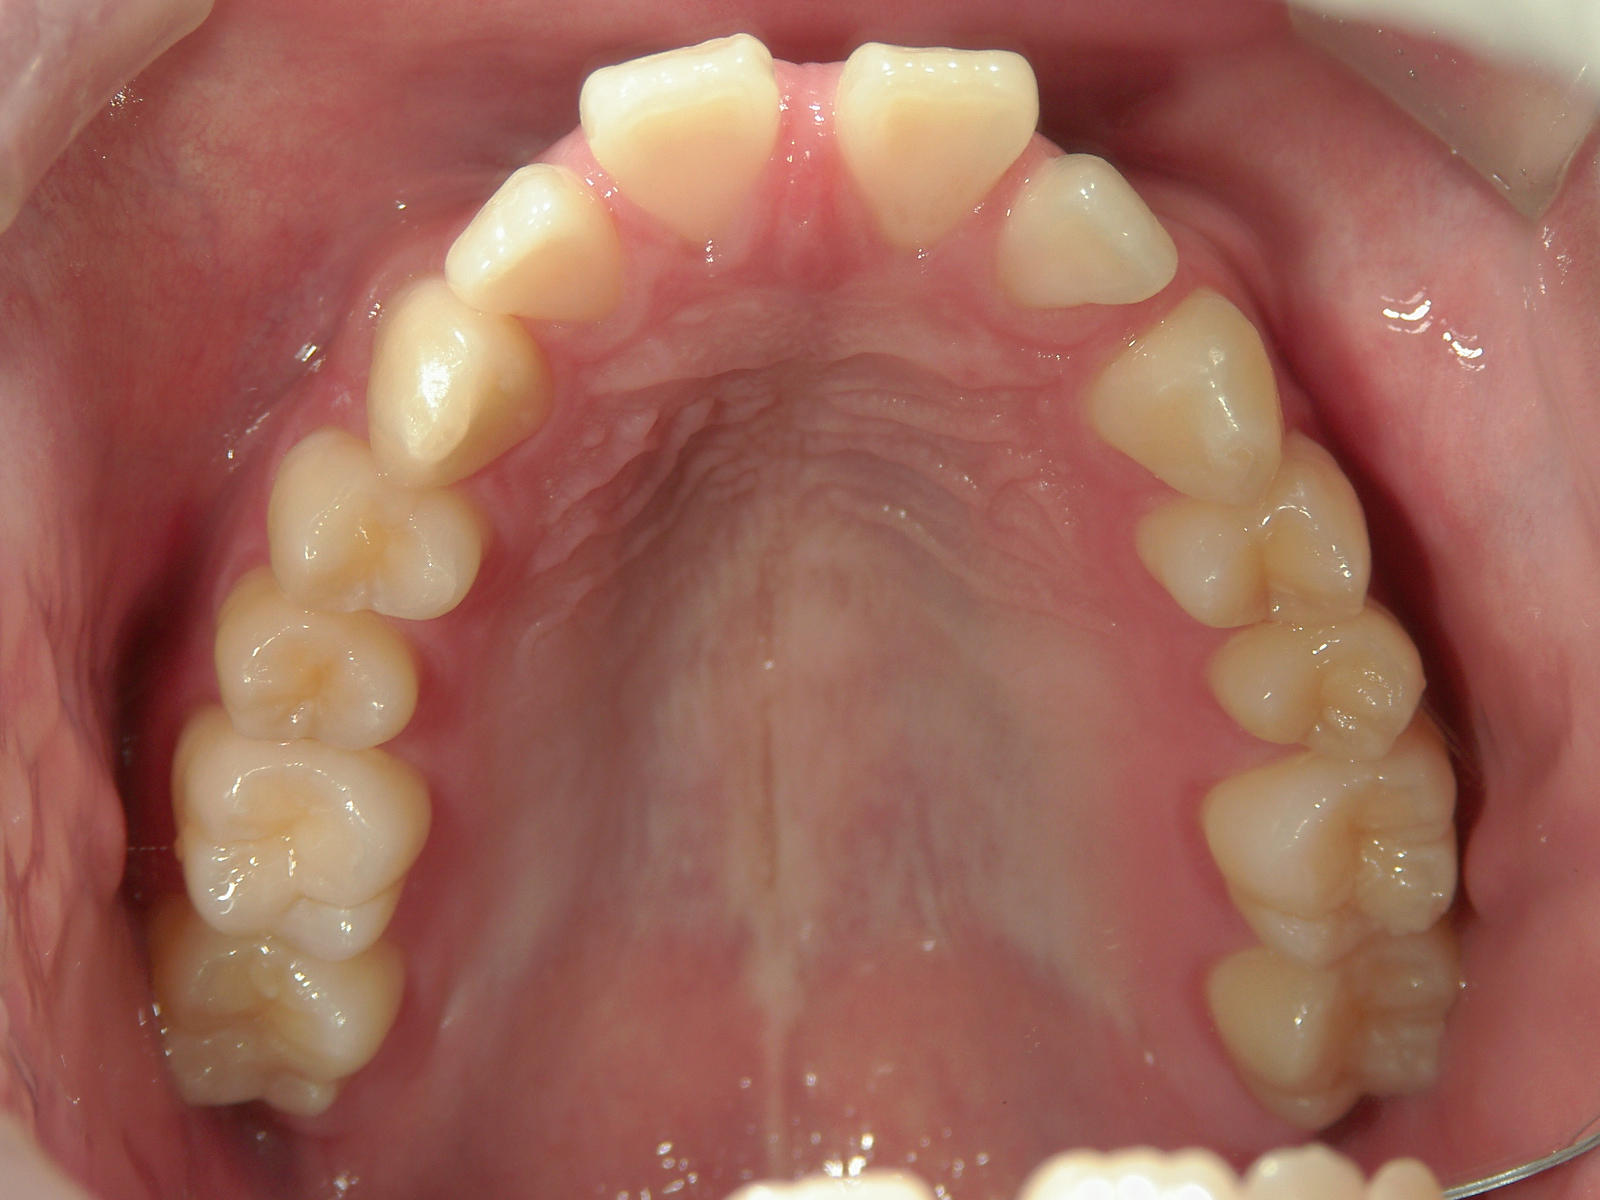

インビザライン矯正 症例(24)

主訴: 前歯の隙間が気になる。

左右上 第一小臼歯(2本)を抜歯。

スライスカットを併用。

カテゴリー : 隙間がある(空隙歯列)